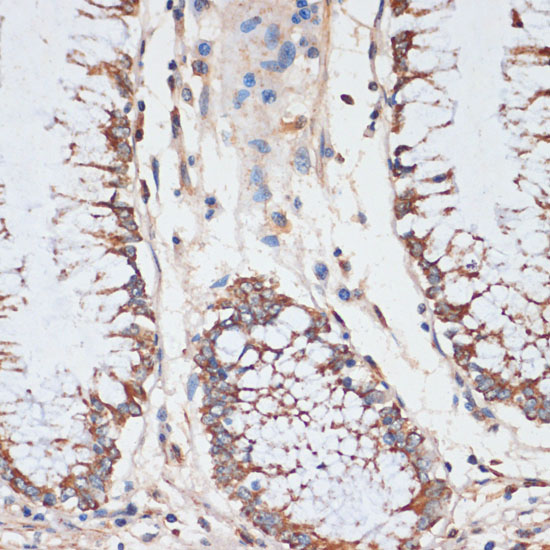

Immunohistochemistry of paraffin-embedded human colon using CDK4 antibody.